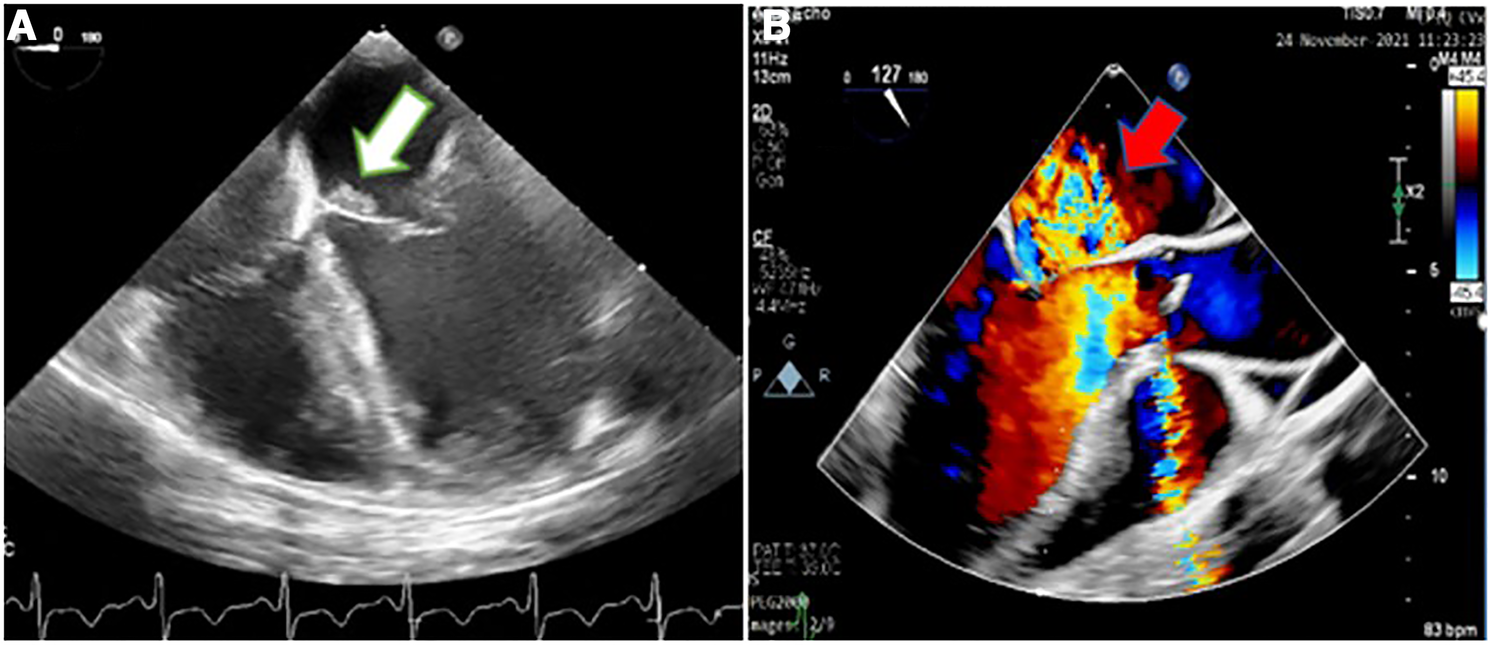

Considering the easily audible systolic and diastolic murmurs on cardiac auscultation, two- and three-dimensional transthoracic and transesophageal echocardiography (2D & 3D TTE and TEE) were performed for better assessment, which revealed an irregularly thickened and destructed bicuspid aortic valve (fusion of non-coronary and right coronary cusps), a few small mobile vegetative lesions, and a partially ruptured left coronary cusp of the aorta, resulting in severe aortic regurgitation (Figure 1). The patient had no aortic ectasia or dilation in view of bicuspid aortic valve or any evidence of endarteritis elsewhere. IE involvement of the mitral valve in the base of the anterior leaflet, adjacent to the aortic valve, with severe mitral regurgitation was also evident (Figure 2). A tricuspid regurgitation with moderate severity and severe pulmonary hypertension (60 mmHg), and severe left ventricular dilatation, accompanied by moderate biventricular systolic dysfunction were also detected. The left main coronary artery was dilated on 2D & 3D TEE.

Figure 2

Two-dimensional transesophageal echocardiography showing an irregular thickening over the atrial side of the base of anterior mitral valve leaflet (white arrow) (A) suggestive of the involvement of the mitral valve by infective endocarditis, which caused severe mitral regurgitation, demonstrated in color Doppler flow study (red arrow) (B).